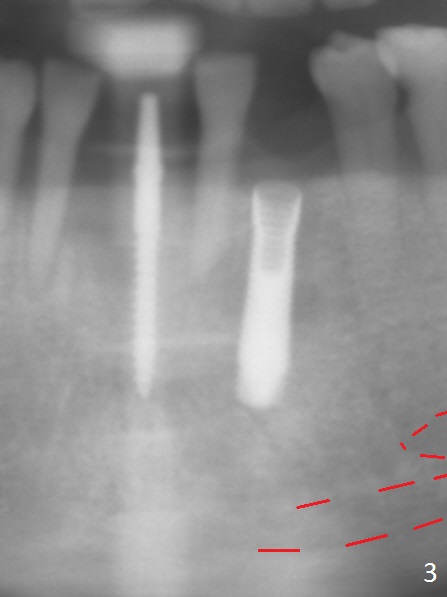

The depth of the osteotomy at #22 is 2-3 mm more than the expected implant length (Fig.2 with 2.7 mm drill in place). The implant at #22 (3.8x18 mm with insertion torque more than 50 Ncm) has clearance from the Incisive Canal and Mental Loop (Fig.3 red dashed line). Allograft with Osteogen is placed around the implants (Fig.4 *) in addition to Osteogen plug (cut in a thin layer) placed against the buccal wall of the socket at #22 (potential leakage). After suturing (Fig.5) and provisional cementation (Fig.6), periodontal dressing is applied (Fig.7). The implants seem to be ready for impression 4 months postop (Fig.8).